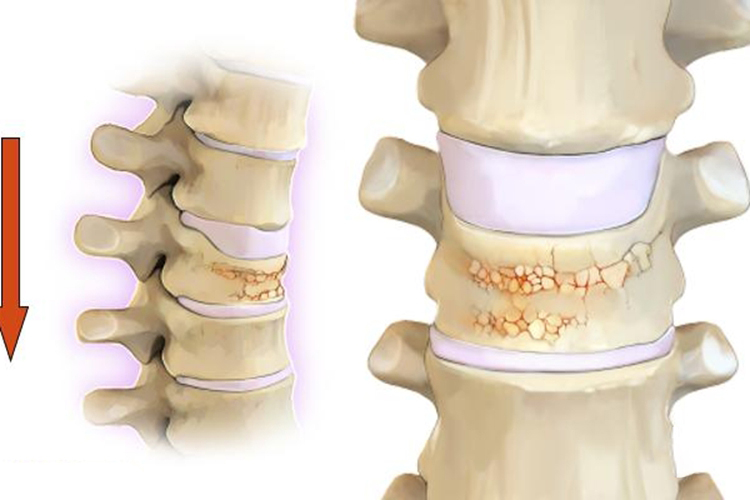

楔形骨折可发生在腰椎、胸椎、颈椎处, 当垂直外力作用时,上下椎体的终板相互挤压,致受压缩力大的椎体前部皮质压缩骨折,随之受累椎体的前缘骨松质也同时被压缩变窄,椎体垂直高度将减小。除椎体受压骨折外,后结构的小关节也可能发生骨折。